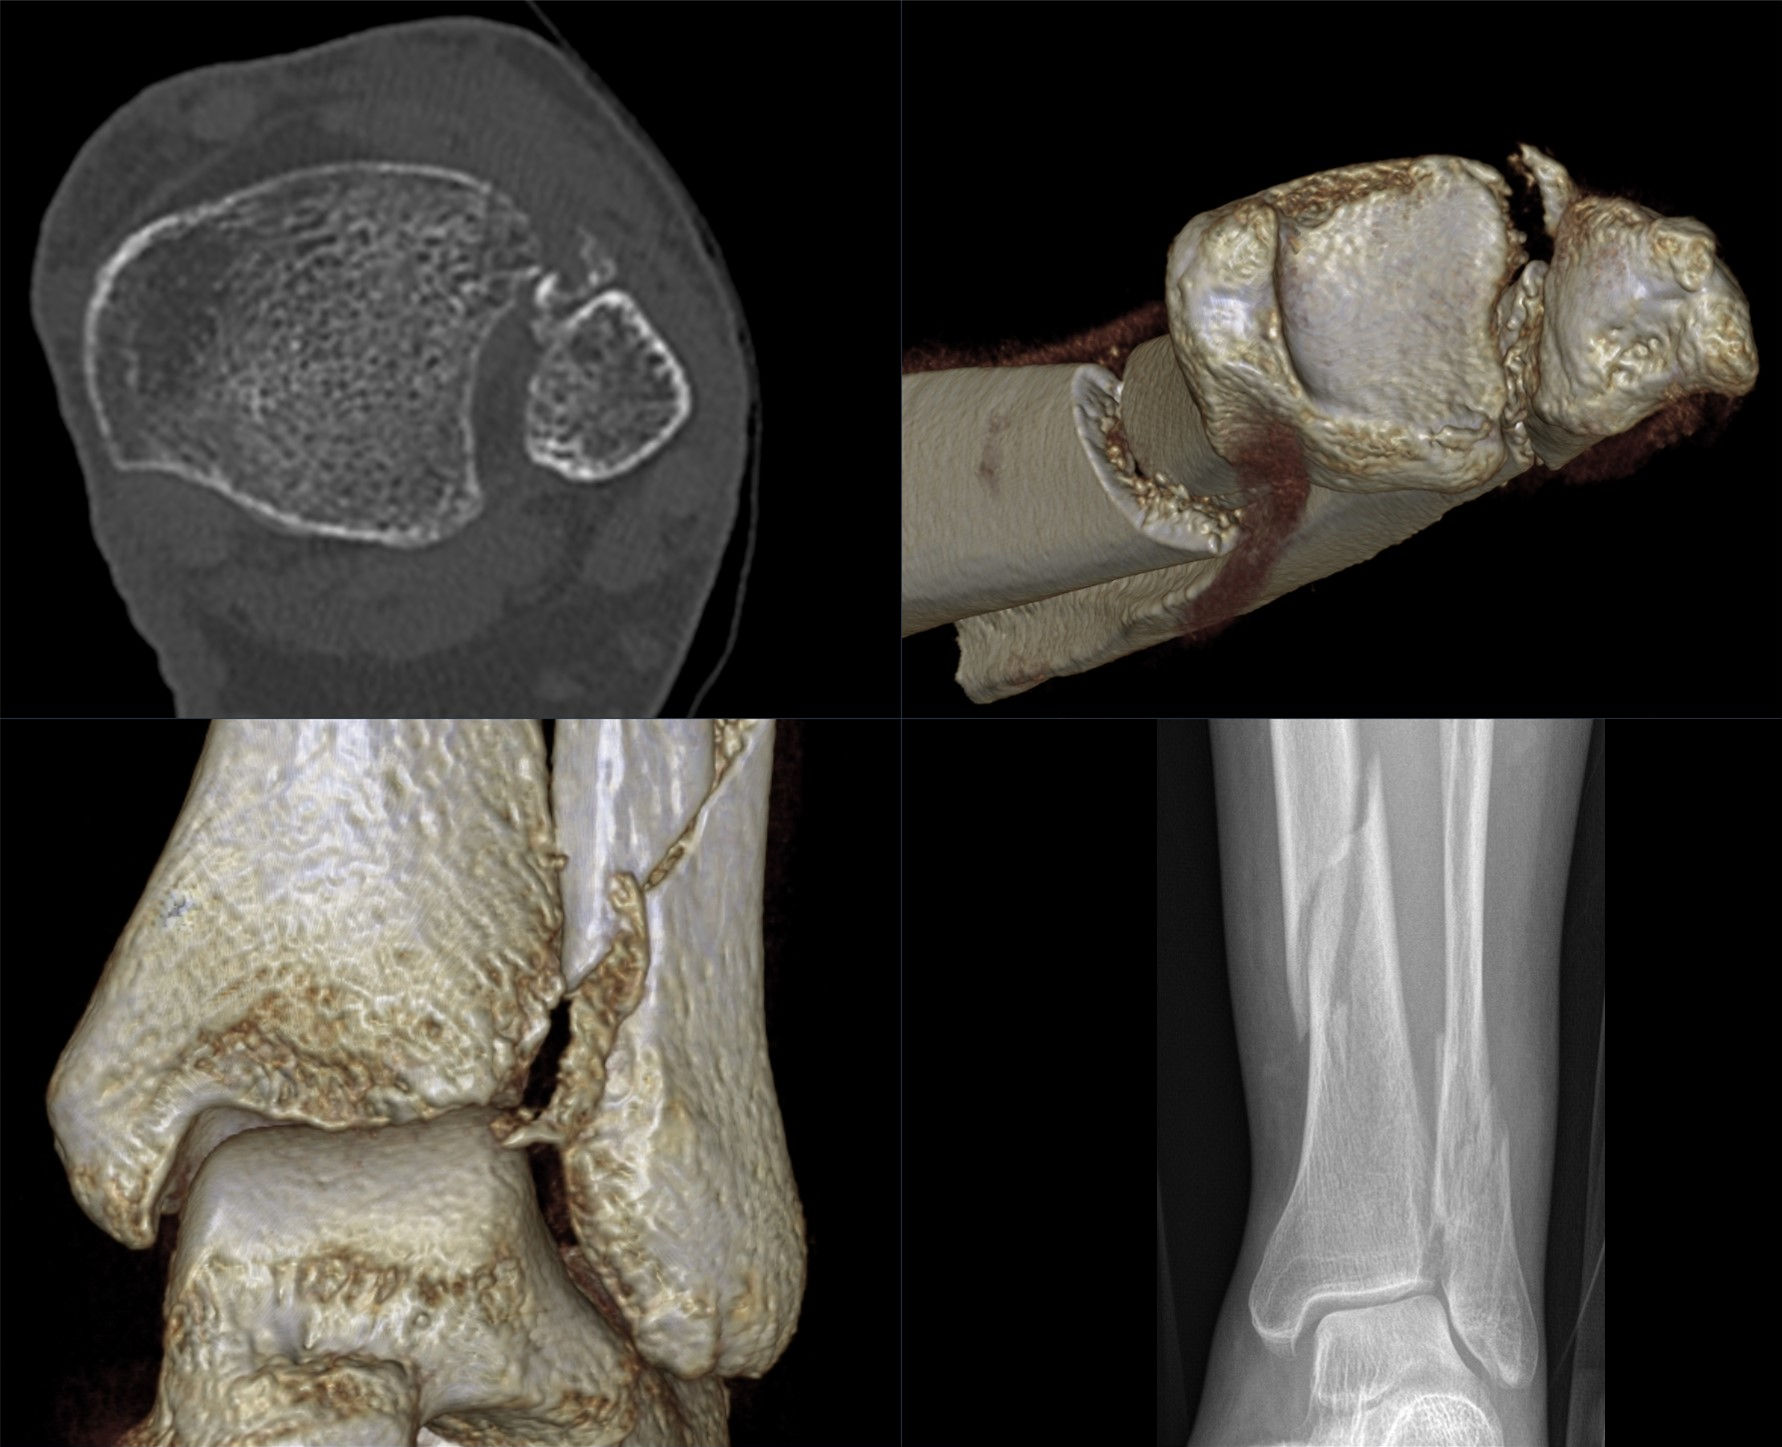

CT검사는 X선을 360도 방향에서 쏘아서 얻는 그림자 영상을 다시 재조합하여 3D형태로 얻을 수 있는 검사입니다.

CT는 보통 크게 두가지 목적을 위해 촬영하게 됩니다.

2) X-ray상 골절이 확실하고, 수술을 계획하는 경우

골절 수술은 일종의 퍼즐맞추기와 같다고 할 수 있습니다. 제자리에서 떨어져나간 뼈조각을 원래 위치에 맞추어 고정을 시켜야 하는 수술입니다. 이를 위해서 수술전에는 내가 어떠한 기구를 이용하여 어느 방향으로부터 진입해서 뼈조각을 고정할 지에 대한 계획을 하게되는데요, 이를 CT 검사를 통해 도움을 받을 수 있습니다. X-ray로도 할 수 있지만은, 앞서 말씀드린 것처럼 그림자만으로 계획을 했을 경우에 만약에라도 발생할 불상사를 예방하기 위해서라도, 좋은 수술 결과를 바란다면 CT검사를 하는 것이 좋습니다.